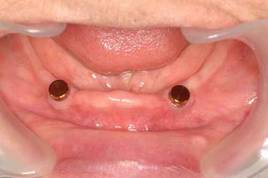

4.下顎無歯顎 インプラントオーバー義歯

義歯内面のマグネット(磁石)が2本のインプラントに固定されるため、入れ歯が安定し、よく噛めるようになります。米国では下顎無歯顎治療の第一選択になっています。

インプラントは虫歯にならないのが特長のひとつです。歯の根に同じ装置をつける方法(オーバーデンチャー)もありますが、虫歯になる欠点があります。

保険外診療ですが、比較的安く済み、カナダでは良く行われているようです。(Zarbはカナダ トロント大学教授)